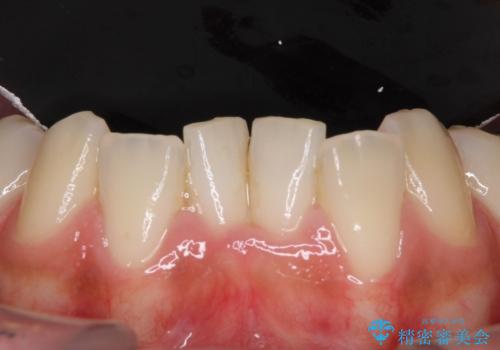

インプラント部は治癒待ちの期間が長くなるため、その期間を利用して下顎の叢生を解消し、より理想的な咬み合わせで補綴治療を行うこととしました。

途中通院されなかった時期が何度かあったため、初診から4年以上の年月がかかりましたが、比較的スムーズに治療を進めることができました。

下顎前歯の歯列を整えたことで、上顎前歯の咬み合わせが安定し、自然な口元に仕上げることができました。